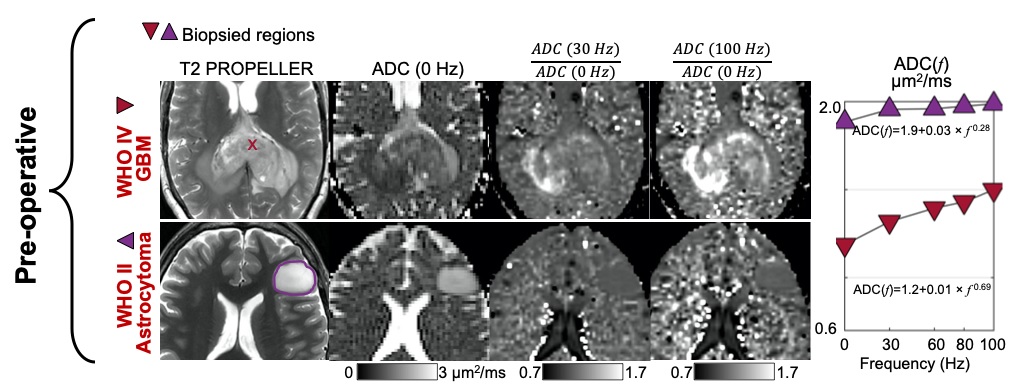

In all four subjects, for regions-of-interest drawn around the brain tumors and the recurrent enhancing lesions, signals from the single-shell multi-frequency OGSE were used to calculate time-dependent diffusivities as the average apparent diffusion coefficient at each frequency, f. For each ROI, the mean ADC(f) was fitted to power-law model, ADC(f) = D0 + A x f θ , in order to estimate the intercept, D0, the dispersion rate, A, and the exponent, θ. There was a significant difference in time-dependent diffusivities between the biopsy-proven high-grade versus low-grade glioma, demonstrating θ of 0.69 and 0.28, respectively (Figure 4). In the post-treatment subjects with recurrent enhancing lesions, one succumbed to recurrent glioblastoma and the other resolved on follow-up imaging, consistent with treatment effects. One of two enhancing lesion ROIs in the recurrent glioblastoma showed greater time-dependence of diffusivity (θ = 0.58) when compared against the enhancing lesion due to treatment effects (Figure 5).

Single-shell multi-frequency OGSE in two subjects with brain tumors before surgical biopsy with a splenial high-grade glioma (top row) and a left frontal low-grade glioma (bottom row). Signal change with different frequencies was fitted to power-law model ADC(f) = D0 + A x f θ in order to estimate the intercept D0, the dispersion rate A, and the exponent θ. The differences in D0 and θ may reflect differences in cellularity (cell density) between the two brain tumors. Higher signal on ADC (100 Hz) / ADC (0 Hz) may reflect higher cellularity and is more conspicuous than on ADC (30 Hz) / ADC (0 Hz).